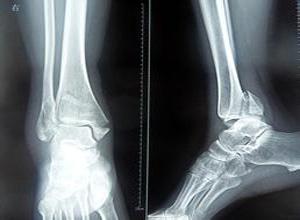

踝部骨折

踝部骨折一般指踝關(guān)節(jié)骨折,踝關(guān)節(jié)由脛腓骨下端與距骨組成。其骨折、脫位是骨科常見的損傷,多由間接暴力引起踝部扭傷后發(fā)生。根據(jù)暴力方向、大小及受傷時足的位置的不同可引起各種不同類型的骨折。目前臨床常用分類方法是Lange-Hansen分類法、Davis-Weber分類法和AO分類法。Lange-Hansen分類法于1950年提出,根據(jù)足在受傷時的位置和暴力的方向?qū)⒐钦鄯譃樾?內(nèi)收型、旋后/外旋型、旋前/外展型和旋前/外旋型四類,每一類又根據(jù)骨折程度及是否伴有韌帶軟組織損傷而分為不同的亞類。該分類對于踝關(guān)節(jié)不穩(wěn)定骨折的閉合復(fù)位有指導(dǎo)意義。Davis-Weber分類法根據(jù)外踝骨折的位置,把踝關(guān)節(jié)骨折分為A、B、C三型,該分類以下脛腓聯(lián)合為界將骨折分為下脛腓聯(lián)合水平以下的損傷(A型)、經(jīng)下脛腓聯(lián)合的腓骨骨折(B型)以及下脛腓聯(lián)合以上損傷(C型),較簡單,使用方便,但卻不能說明整個踝關(guān)節(jié)各種復(fù)雜改變。國際創(chuàng)傷學(xué)會(AO)進一步細化了Davis-Weber分類法,提出了AO分類法。